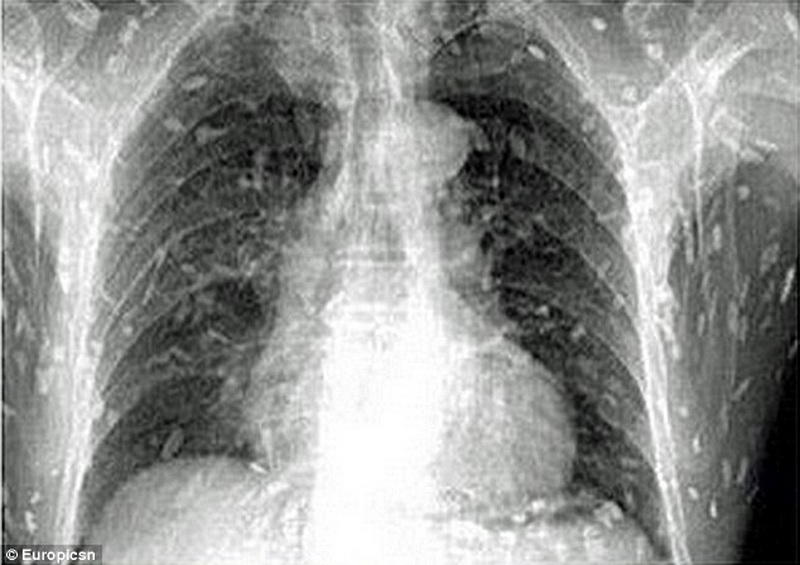

А все началось с того, что китаец пошел к доктору с жалобами на боли в животе и сыпь на коже, передает Day.Az со ссылкой на Soulpost.ru. К его ужасу, рентген показал, что все его тело заражено глистами - солитерами, ленточными червями.

Причина - слишком много сашими, точнее, один неудачно съеденный зараженный кусок сырой рыбы.